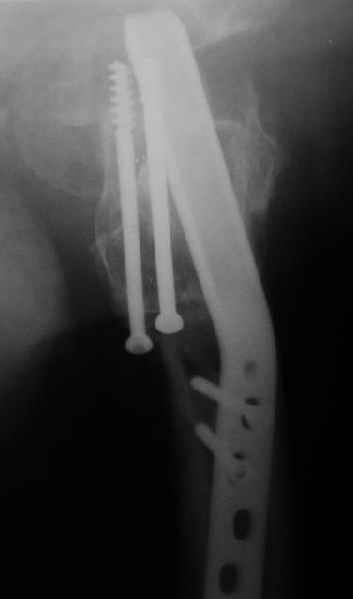

Мужчину 56 лет оперировали у нас в августе 2003 г. - вальгизируюшая остеотомия из-за позднего (через 2 мес. после травмы) поступления с переломом шейки бедра (картинки 1,2). Курильщик, соматической патологии не было. Сейчас поступил с жалобами на проблемы в области тазобедренного сустава, на снимках 3,4 видно вырезывание клинка.Чтоб можно посоветовать в этой ситуации? Заранее спасибо.

A male 56 years old was operated in Aug 2003 - valgus osteotomy performed because of delayed admission with neck fracture (2 months) images 1,2. Smoker, no other major medical problem. Now he re-admitted with the images 3,4.What would you do in the situation?THX in advance.

По-моему, проблема не только в вырезывании клинка, но и в развитии аваскулярного (асептического) некроза головки бедра. Его развитие, кстати, представляется вполне закономерным при предпринятой тактике. Считаю наиболее рациональной тактикой сейчас удаление всех конструкций, реостеотомии (если само не развалится) на прежнем месте и тотальное эндопротезирование с использованием длинной ножки дистальной фиксации с воротником без цемента. Проксимальный фрагмент при этом будет являться аутотрансплантатом, нанизанным на ножку. После операции предписать более щадящий реабилитационный режим (ходьба с костылями месяцев до 4-х).

Сама собой просится идея о тотальном эндопротезировании тазобедренного сустава протезом по типу онкологического (обычный "сажать" уже некуда). Аргументы:

1. Налицо рентгенологическая картина коксартроза. Деформирована головка, суставная щель сужена и т.д.

The osteotomy seems to be showing bony union. (New bone at the medial aspect). There is a big step in the union. The distal fragment is way out laterally.There is overiding of the neck over the head. The screws are out superiorly and the blade also coming out. There is no union of the neck fracture. The head does not seem to be normal- distorted in shape and probably starting of AVN too.